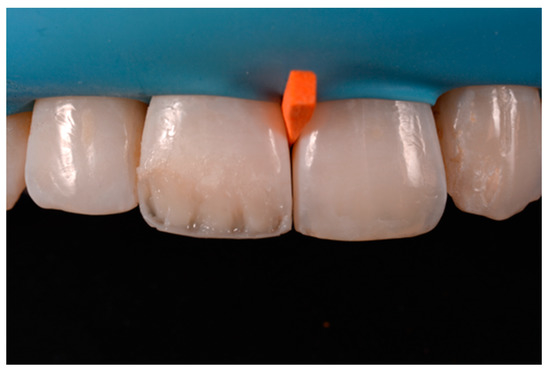

Figure 38.

At 1.5 years, post-operative clinical view. Reprinted from Restauri diretti nei settori anteriori, G. Paolone, S. Scolavino, © 2021, with permission from Quintessence Publishing Italy.